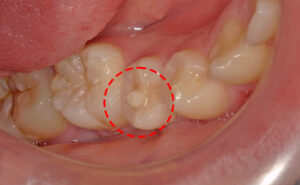

3.奥歯の溝乳歯の奥歯の溝は深く、虫歯菌が溜まりやすい形状をしています。溝が深いと歯ブラシが奥まで届かず、虫歯菌が残ってしまうため、虫歯が進行しやすくなります。仕上げ磨きを行う際は、特に丁寧に磨くことを心がけましょう。 |

![]() |

特徴④:萌出直後の奥歯の溝の深さ奥歯の噛み合わせの溝が深く、歯ブラシが届きにくいため、汚れが溜まりやすく、虫歯になりやすいです。数年経つと咬む面が摩耗してきて、溝が浅くなり虫歯になりづらくなります。従って萌出直後が1番虫歯になりやすいです。 |

5.シーラントの活用奥歯の噛む面には深い溝があり、食べかすや汚れがたまりやすいため、虫歯のリスクが高い部位です。こうした溝を歯科用の材料であらかじめ埋める「シーラント処置」を行うことで、汚れが入りにくくなり、効果的に虫歯を予防することができます。 |